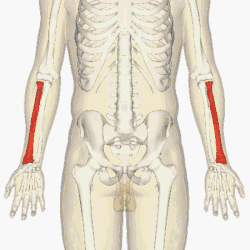

![]() The radius (shown in red) is a bone in the forearm. | |

The radius or radial bone (pl.: radii or radiuses) is one of the two large bones of the forearm, the other being the ulna. It extends from the lateral side of the elbow to the thumb side of the wrist and runs parallel to the ulna. The ulna is longer than the radius, but the radius is thicker. The radius is a long bone, prism-shaped and slightly curved longitudinally.